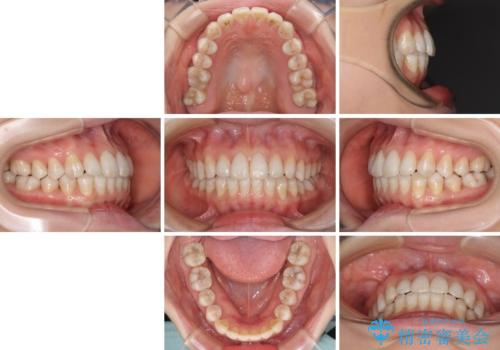

話しにくいオープンバイト インビザラインによる矯正治療

- 前歯の上下スペースによる話しにくさを気にして来院された患者様です。

インビザラインにより上下の前歯の隙間を閉じていくこととしました。

上下の奥歯を圧下させるようにすることで、前歯を接触させるように計画しました。

隙間に舌が入り込むことが話しにくさに繋がっていたため、舌の筋肉のトレーニングも並行して行い、話しにくさの改善と後戻りの抑制を図りました。